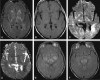

F<sc>ig</sc> 1.

Fig 1.

Patient with isolated restricted diffusion. A and B, DW image (A) and ADC map (B) show restricted diffusion in the PLIC. C and D, Findings on corresponding FLAIR image (C) and contrast-enhanced T1WI (D) are unremarkable.

F<sc>ig</sc> 2.

Fig 2.

Isolated restricted diffusion in a patient who recovered without residual symptoms. A, DW image shows asymmetric (right greater than left) high signal intensity in the superior corona radiata and subcortical white matter. B, Corresponding ADC map shows subtle low signal intensity. C, No abnormalities are present on the FLAIR image.